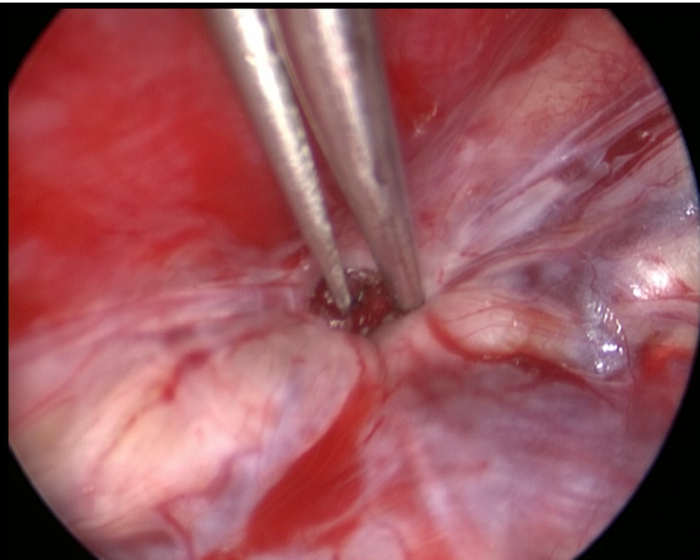

手术的小切口下应用30度神经内镜的独特视角,吸除囊液,观察囊腔(如下图示),囊壁有数根囊壁化的骶神经显微,充满囊液后对其有压迫作用。